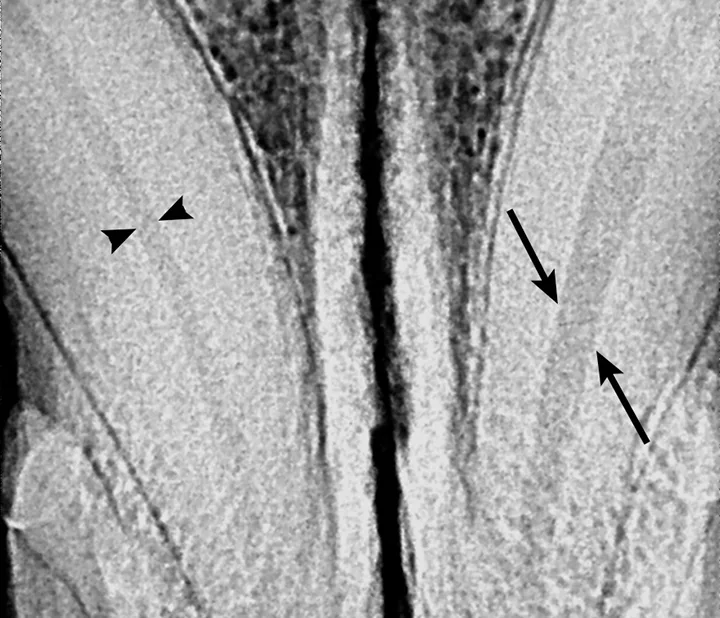

Figure 7

The pulp chamber of the left mandibular canine (arrows) is significantly wider than the right (arrowheads), indicating that the pulp is no longer producing secondary dentin and is nonvital. Although this is a definitive sign of nonvitality, its absence does not confirm vitality.